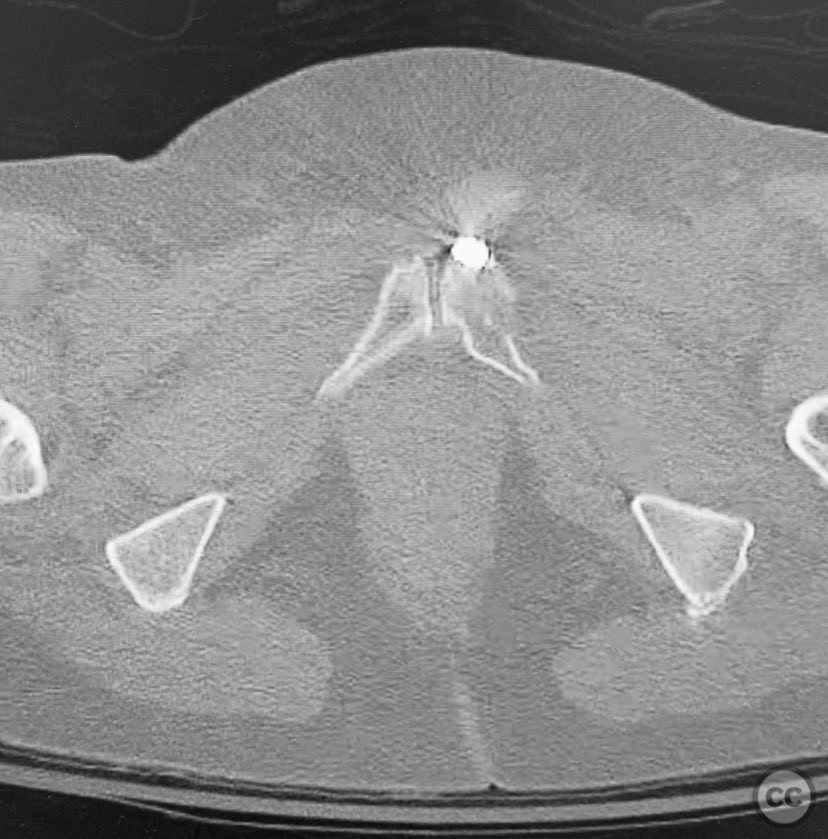

Anatomical surgical approach:  Percutaneous technique was employed. Small stab incisions were made over the lateral aspect of the pelvis. Under continuous fluoroscopic guidance, guidewires were advanced through the ilium into the sacrum (iliosacral region) and through the superior pubic ramus. Cannulated screws were then inserted over the guidewires, ensuring extra-articular and intraosseous positioning within the safe bone corridors as determined by preoperative CT analysis.

Orthopaedic implants used:   Cannulated iliosacral screw, cannulated pubic ramus screw